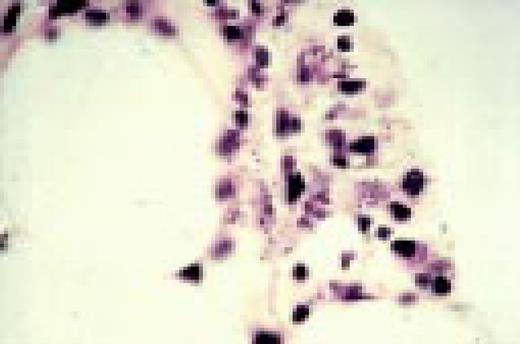

Slide L42

IgA myeloma, bone marrow biopsy. Several of the plasma cells contain intranuclear inclusions referred to a Dutcher bodies. These structures are found in a wide spectrum of immunoproliferative disorders and had been most frequently associated with plasmcytoid lymphomas. They lack specificity for any subtype of the immunoproliferative processes.FIG42